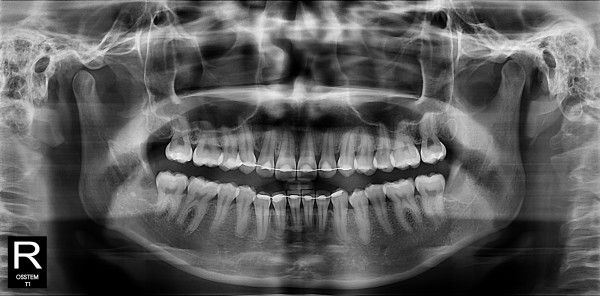

사랑니발치 10대/여성

5e20e086184bc11a2d853605b7813944_1764319801_4302.jpg